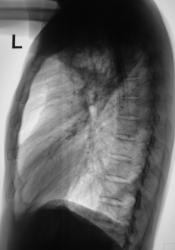

Пациент в 2007, 2008 гг. проходил профилактическую флюорографию - иллюстрации ниже. При прохождении флюорографиив 2009 г. "картинка" резко отличается от предыдущих.

Произвели дообследование пациента согласно стандарту.

По поводу личного мнения - больше склоняюсь, пока, в сторону абсцесса, однако сомнения терзают и весьма.

Очень похоже,но при микроскопии "палки" не выявлены. Фтизиатр занимается пациентом вплотную. Уже рентгенологически обследовано "окружение" пациента, договорились с областной туб. больницей по поводу госпитализации. Но, вот полость какая-то не совсем типичная, хотя локализация и общий вид верхушки прямо указывают на "специфику".